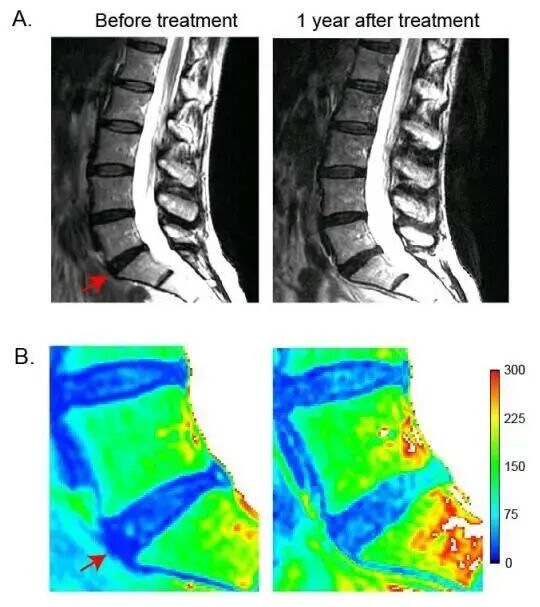

我们常说的腰间盘突出,也就是医学上的椎间盘突出,多发生在腰4腰5和腰5骶1突出。这是腰椎骨之间腰间盘发生退行性改变或者由于急性外伤导致纤维环破裂髓核流出所致,如果突出压迫到了神经就会导致腰臀腿疼痛、发麻的情况。腰椎间盘因为其特殊结构和材料的关系,使得它们的年龄周期只有20年的健康寿命,所以腰间盘突出也属于退行性病变。什么是退行性疾病呢?简单来说就是随着年龄增长,机体开始老化,椎间盘也会老化就很容易破裂突出,再加之姿势不正确,不注意锻炼等后天环境影响,更加速了椎间盘的老化突出。一旦发生了突出,就无法彻底根治,只能通过各种理疗来缓解症状,对于大多数人来说哪怕只是轻度的疼痛,也很影响正常的生活学习。临床上尽管疗法众多,但都无法彻底根治,这也使得腰间盘突出成为了难治性疾病,临床亟需新的修复策略。尽管大部分患者都可以自行缓解,但对于重症患者来说,却严重影响了他们的生活,甚至成为了缠绕一生的病痛。近年来,对于退行性腰椎间盘疾病病理生理学的理解进展,促进了新的生物疗法的研究,包括基于细胞的策略。这些干预方式的潜在优势是保留了正常的周围解剖结构、生物力学和运动。细胞疗法在体外和体内都产生了令人兴奋的结果,而间充质干细胞的研究也变得特别有前景。《Transplantation》上的一项研究中,研究人员招募了10名患者,所有患者均患有严重型腰椎间盘突出,且在招募前至少6个月对常规治疗无应答,并伴有保留外部纤维环和持续性腰痛。患者被1:1随机分入细胞组和对照组,在局部麻醉下,细胞组患者回输MSC(每个椎间盘回输含25×106 MSC的2mL生理盐水),对照组患者回输2mL 1%甲哌卡因对靠近病变椎间盘的椎旁肌肉组织进行浸润。与对照组相比,接受MSC修复的人群在腰椎疼痛(VAS)和功能障碍(ODI)方面显示出了快速而显著的改善。镇痛效果明显,有效率接近71%,且疼痛的改善也提高了患者的生活质量。此外,研究者还发现,MSC干预修复的人群中,Pfirrmann分级量化的退行性病变得到改善,而对照组却发生了恶化。干细胞具有组织分化和再生的功能,间充质干细胞与髓核细胞的共培养刺激髓核细胞增殖和间充质干细胞向软骨细胞谱系分化,细胞因子的产生和增加,尤其是转化生长因子有利于促进细胞的转化。更重要的是,干细胞的干预修复无需手术,不会产生解剖结构的改变,也不会妨碍进一步的临床干预,其安全性也早在多项临床试验中被证实,在这项临床试验为期一年的修复过程中,也并未发生什么不良反应,这都证明了干细胞的安全性、可行性和临床疗效。总之,该项临床研究证明了使用扩增的间充质干细胞干预调理腰椎间盘退变引起的慢性腰疼是一种可行的策略。干细胞的干预修复更简单、保守,无需手术或患者住院就能更好的缓解疼痛症状。这对未来临床干预提供了新的方向选择,相信随着干细胞研究的不断深入,干细胞将会帮助更多人减轻疾病所带来的痛苦,从而产生更多、更长远的益处。